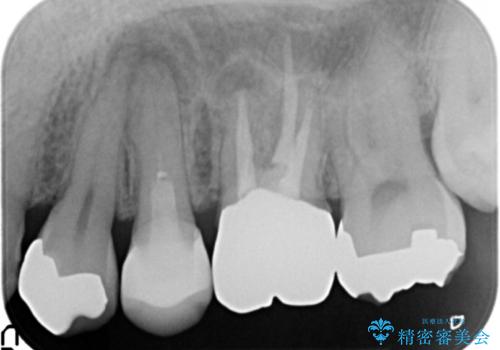

セラミックインレーと根管治療を伴うセラミッククラウン

- 根管治療の難易度が高く他院で放置か抜歯を提案され、治療をご希望され当院へと来院されました。

X線写真より大きな根尖病変が認められ根管治療および補綴処置、手前の歯は虫歯の再発による銀歯のやりかえが必要な状態です。